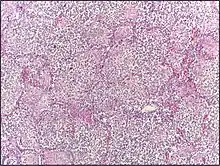

Micrograph of lobar pneumonia, H&E stain.

Lobar pneumonia usually has an acute progression. Classically, the disease has four stages:[1]

• Congestion in the first 24 hours: This stage is characterized histologically by vascular engorgement, intra-alveolar fluid, small numbers of neutrophils, often numerous bacteria. Grossly, the lung is heavy and hyperemic.

• Red hepatization or consolidation: Vascular congestion persists, with extravasation of red cells into alveolar spaces, along with increased numbers of neutrophils and fibrin. The filling of airspaces by the exudate leads to a gross appearance of solidification, or consolidation, of the alveolar parenchyma. This appearance has been likened to that of the liver, hence the term "hepatization".

• Grey hepatization: Red cells disintegrate, with persistence of the neutrophils and fibrin. The alveoli still appear consolidated, but grossly the color is paler and the cut surface is drier.

• Resolution (complete recovery): The exudate is digested by enzymatic activity, and cleared by macrophages or by cough mechanism. Enzymes produced by neutrophils will liquify exudates, and this will either be coughed up in sputum or be drained via lymph.